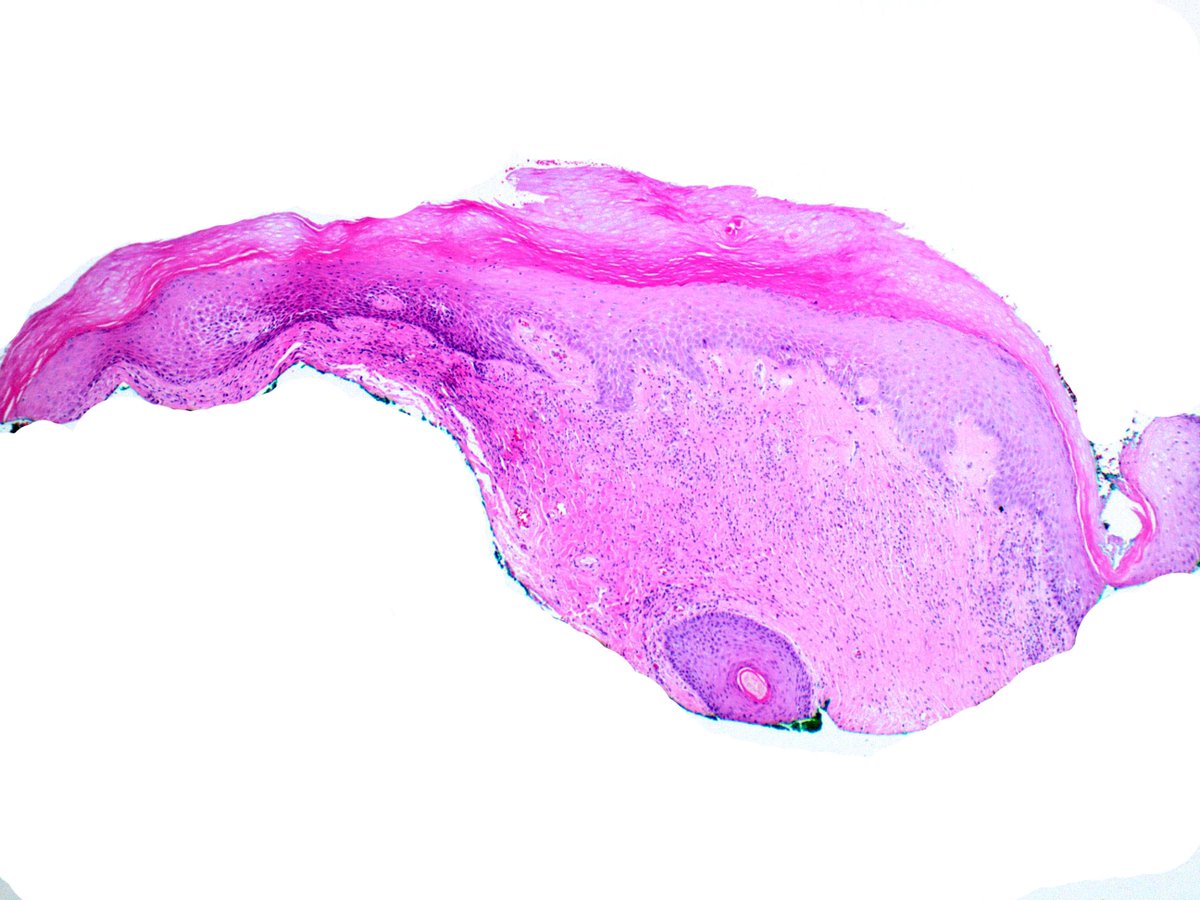

It seems like a banal SCC with keratoacanthomatous features, but it is a drug reaction pattern to treatment for metastatic melanoma with BRAF inhibitor. Take care

#dermatology#oncology#dermpath#dermatopathology#patologia#patología#pathologypic.twitter.com/ayrciZL6cL